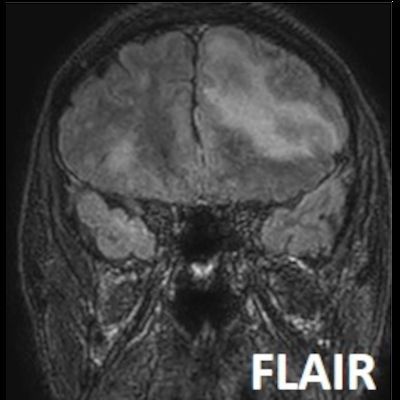

- Bilateral asimetrik subkortikal ve derin beyaz cevherde T1 ağırlıklı görüntülerde belirgin hipointens (oklar), T2A görüntülerde hiperintens (oklar), gri cevhere bakan kesimi düzgün (oklar), DAG’de hiperintens (ok) lezyonlar izlendi. Lezyonlarda T2/FLAIR uyumsuzluğu vardı (ok). Serebellar beyaz cevherde dentat nukleusu koruyan hilal işareti görüldü (ok başı). SWI sekansta sol motor kortekste hipointens kronik glioinflamatuar reaksiyon ile uyumlu sinyal değişikliği izlendi (ok başı).

- PML lezyonları, T1A görüntülerde belirgin hipointenstir. Gri cevhere bakan yüzleri keskin olup T2/FLAIR uyumsuzluğu önemli özelliğidir.